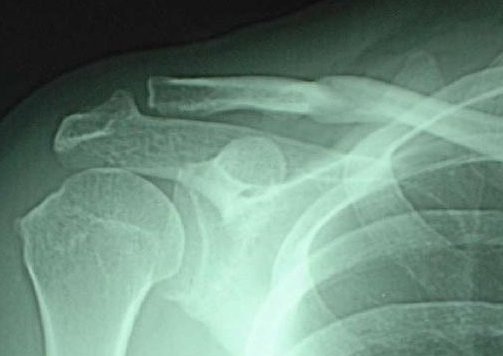

以下はネットから拾ってきた写真、折れ方がよく似ているので掲げておくよ。